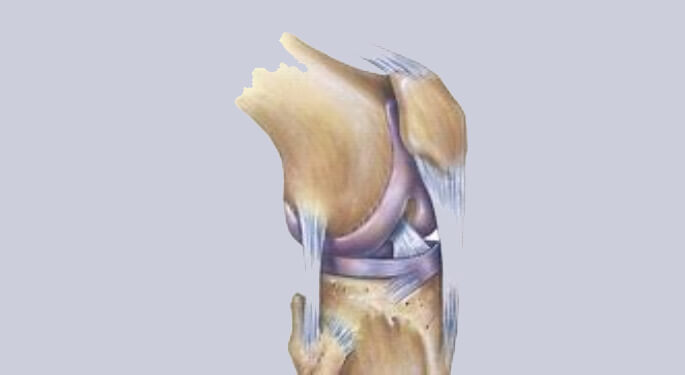

De belangrijkste steunende structuren (ligamenten) bestaande uit de

- Mediale band (mediaal collateraal ligament)

- Laterale band (lateraal collateraal ligament) dewelke buiten het gewricht (extra-articulair) zijn gelegen

- Voorste kruisband

- Achterste kruisband dewelke binnen het gewricht (intra-articulair) zijn gelegen

Deze structuren staan primair in voor de stabiliteit van de knie en begeleiden de knie tijdens de complexe plooi-strek activiteit welke gepaard gaat met een rotatiebeweging van het femur ten opzichte van de tibia